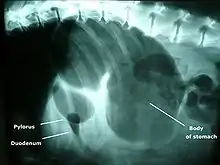

La dilatation de l'estomac par de l'air précède généralement sa torsion[1]. La dilatation résulte d'une ingestion d'air par aérophagie associée à une accumulation de gaz dans l'estomac. La torsion se produit le plus souvent dans le sens horaire, selon une rotation comprise entre 90 et 360°[1]. Le pylore passe de droite à gauche tandis que l'omentum devient ventral[2].